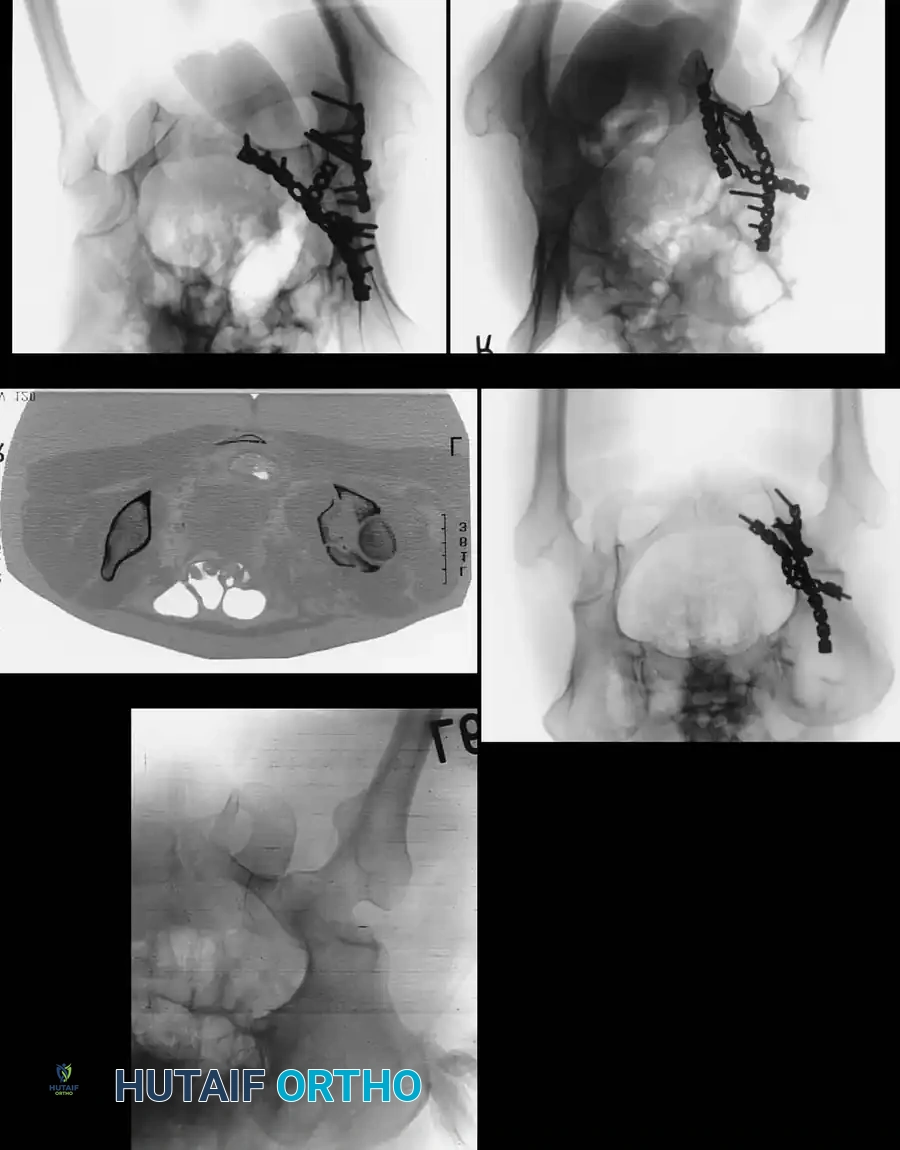

Advanced Imaging: Computed Tomography (CT)

While plain radiographs provide the foundation for classification, fine-cut CT scanning with 2D multiplanar and 3D surface-rendered reconstructions is the gold standard for modern surgical planning.

Image

CT imaging excels at identifying:

* Intra-articular osteochondral fragments (loose bodies).

* Marginal impaction of the articular cartilage.

* The exact size and comminution of posterior wall fragments.

* The orientation of fracture lines to plan optimal screw trajectories.